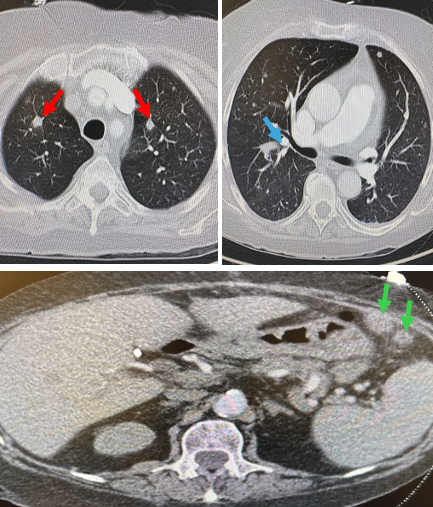

Case: A 65-year-old woman with end-stage renal disease status post renal transplant and on chronic immunosuppression presented with two days of worsening dyspnea. She was hypotensive and tachycardic but afebrile and without leukocytosis. TTE showed a moderate pericardial effusion with early tamponade physiology and a partially mobile 1.8 × 1.0 cm mass attached to the posteromedial papillary muscle, interpreted as tumor or thrombus (Figure 1). Cardiac MRI was recommended but deferred due to instability. CT chest with contrast revealed several pulmonary nodules, two masses in the right breast, and an enlarged mediastinal lymph node—findings suggestive of widespread malignancy (Figure 2). The patient then exhibited altered mental status, prompting a CT scan of the head, which identified ring-enhancing lesions in the brain (Figure 3). Subsequently, samples of blood and pericardial fluid revealed the presence of disseminated Aspergillus fumigatus.